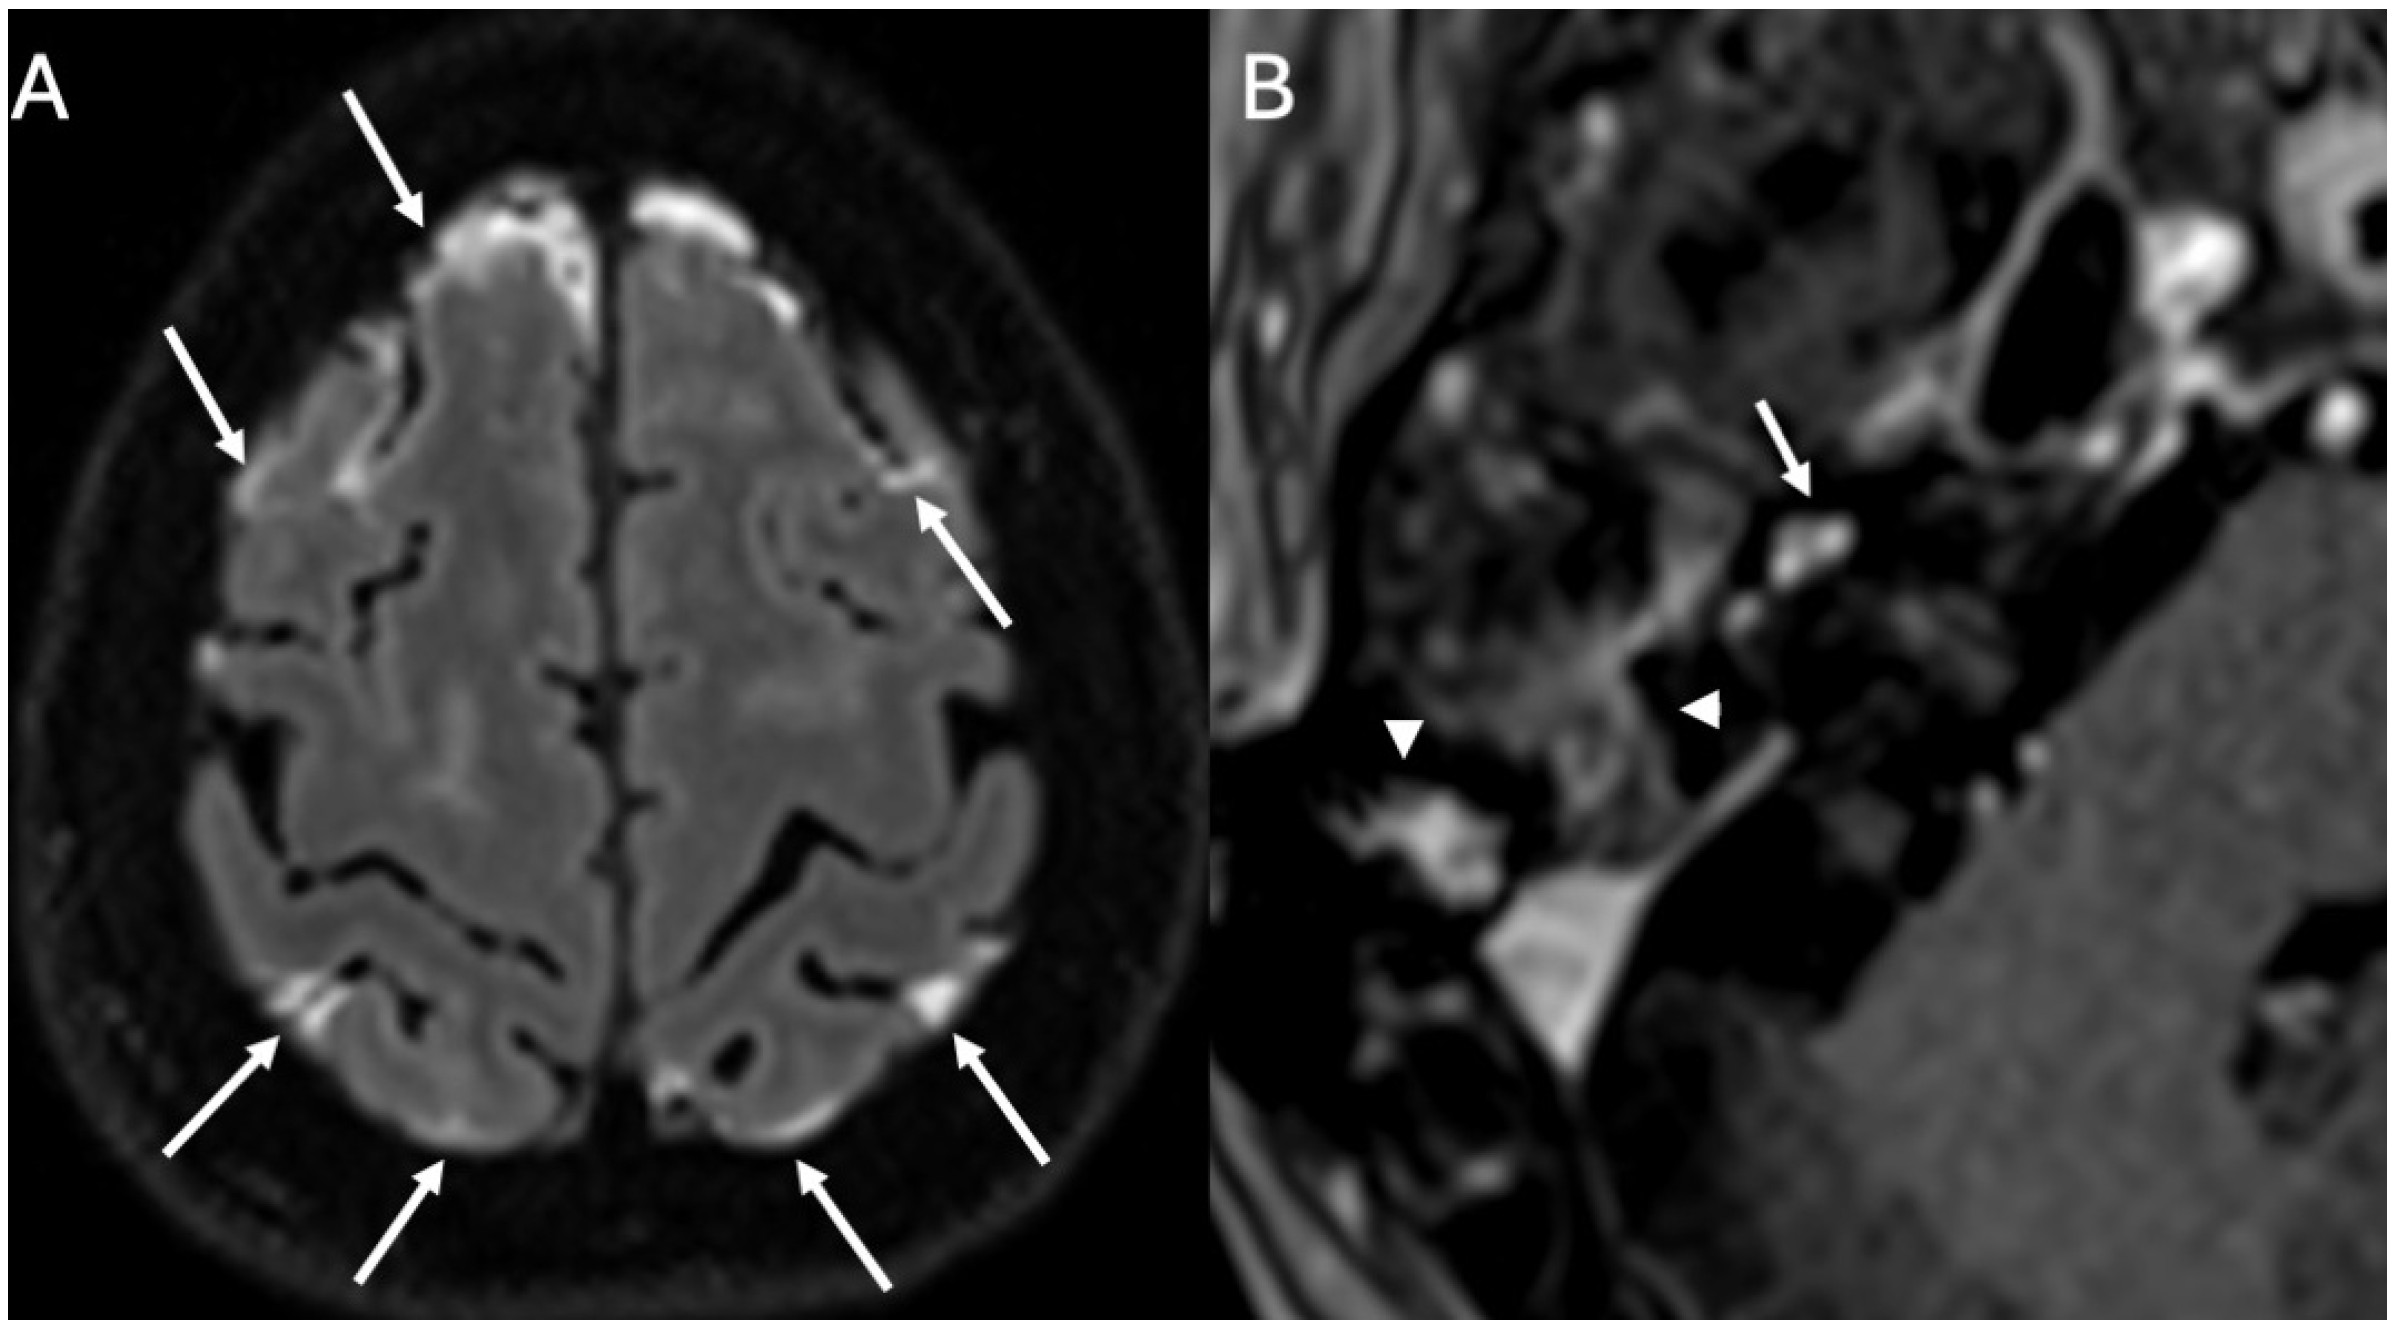

3.4. Labyrinthitis and Vestibulocochlear Neuritis

Imaging

| Labyrinthitis/Vestibulocochlear Neuritis | Taxak & Ram 2020 [32]; Kharrat et al., 2024 [33]; Singh et al., 2023 [34]; Kim et al., 2024 [35] | Case reports and small series | Meningitis can cause secondary labyrinthitis with cochlear enhancement on MRI; progression to ossification possible if chronic. |